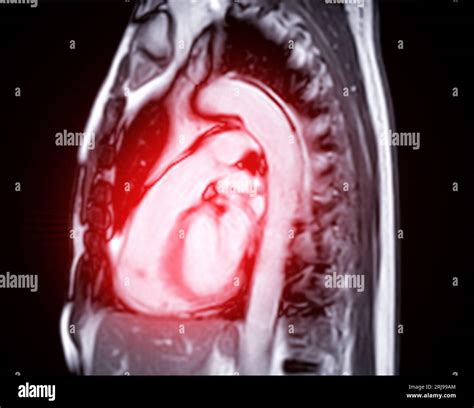

Interpreting the results of an MRI of heart involves a detailed analysis by a radiologist or cardiologist. The images provide information about:

• The heart's structure, including the chambers, valves, and blood vessels.

• The heart's function, such as ejection fraction and wall motion.

• Any abnormalities, such as scarring, inflammation, or tumors.